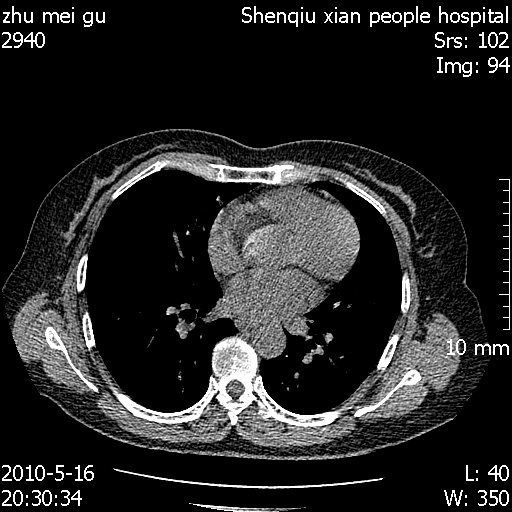

标题: CT26733:能否诊断支扩?

患者,女,62岁,有反复咯血史10年,近三年来大咯血数次,每次量在500-1000ml

图像不全。右中叶内侧段陈旧性病灶。

支持:图像不全。右中叶内侧段纤维、钙化灶。

窗宽、窗位应该适宜。

右中叶内侧段慢性感染性病变,不排除合并支气管扩张可能。

右中叶内侧段纤维、钙化灶.

建议hrct